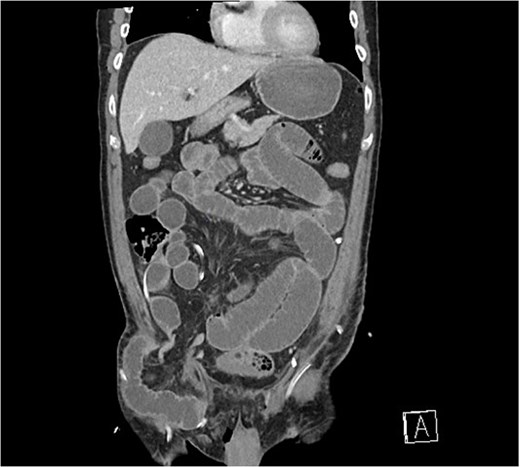

Progressive abdominal distension with obstipation was noted on post operative day 1. Clinical examination and an urgent CT scan of his abdomen and pelvis revealed small bowel obstruction due to herniation behind the lateral aspect of the inguinal ligament into the femoral triangle, lateral to the femoral neurovascular bundle (Fig. 1).

Coronal CT scan demonstrating small bowel herniating below the inguinal ligament, lateral to femoral vessels.